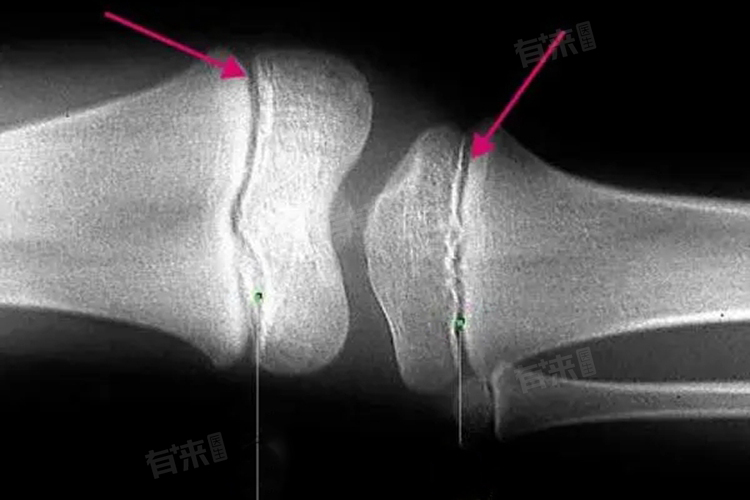

1、骺线形态:在儿童生长发育期,骨骺与干骺端之间存在软骨,X线片上表现为一条透光带,即骨骺线。幼儿时期,骨骺线较宽,随着年龄增长逐渐变窄。当骨骺与干骺端的软骨完全骨化后,骨骺线会消失,形成一条紧密的缝,这标志着骨骼发育的基本完成。

3、骨骺损伤表现:不同类型的骨骺损伤在X线片上有不同表现。Ⅰ型骨骺分离,X线征象主要是骨化中心移位,复位容易,预后良好;Ⅱ型骨骺分离伴干骺端骨折,多见于桡骨远端、肱骨近端及胫骨远端,骨折线通过肥大并累及干骺端的一部分,骨折片呈三角形;Ⅲ型骨骺骨折,属于关节内骨折,骨折线从关节面开始穿过骨骺,再平行横越部分骺板的肥大层;Ⅳ型骨骺和干骺端骨折,骨折线呈斜形贯穿骨骺、骺板及干骺端,易引起生长发育障碍和关节畸形;Ⅴ型骺板挤压性损伤,早期X线表现常为阴性结果,多在晚期发生生长障碍时才能作出诊断。